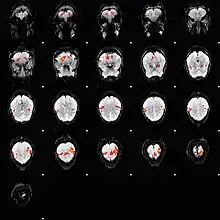

L'imagerie par résonance magnétique fonctionnelle repose sur la mesure du signal BOLD.